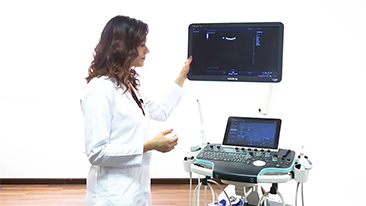

Sejak didirikan, Mindray terus mencari cara baru untuk meningkatkan keandalan diagnostik. Didukung Teknologi ZONE Sonography? terkini, platform ZST+ baru Resona 7 meningkatkan kualitas gambar ultrasound melalui pengambilan zona dan pemrosesan data saluran.

Selain kualitas gambar premium, Resona 7 juga meningkatkan kemampuan penelitian klinis dengan V Flow revolusioner untuk evaluasi hemodinamika vaskular, serta pengambilan penampang tercanggih dari rangkaian data 3D untuk diagnosis CNS pada janin. Kombinasi pengoperasian multisentuh berbasis gerakan yang paling intuitif dengan semua fitur klinis penting membuat Resona 7 menjadi gebrakan baru dalam inovasi ultrasound.